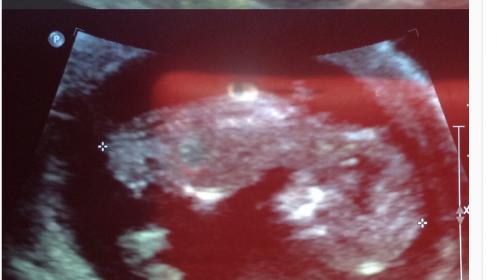

Is this really an obvious boy? 12 weeks